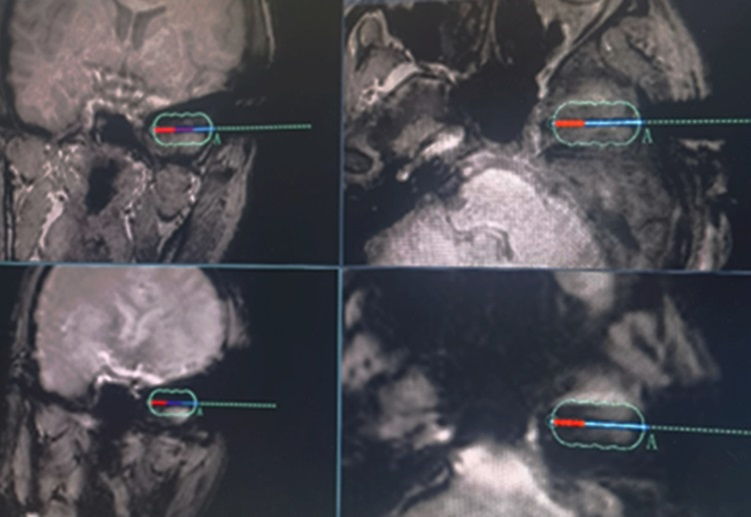

1月15日,兰大二院神经外科张新定教授团队为1例难治性癫痫患者成功实施了甘肃省首例核磁共振引导下的激光间质热疗术(LITT)。

患者为30岁男性,癫痫病史长达28年,诊断为药物难治性癫痫。1年前在兰大二院行癫痫多模态术前评估,颅内立体脑电图(SEEG)结果确定为颞叶癫痫,同期行SEEG引导的射频热凝术,短期疗效良好。为了在不开颅手术的情况下达到精准和微创治疗目的,功能神经外科团队经过充分评估,联合神经内科、核磁共振科、手术麻醉科及院外专家进行了多学科讨论,制定了周密的手术方案和操作流程。术中,首先在神经外科机器人的引导下植入热凝光纤,在核磁共振设备上连接LITT设备,最后在核磁实时监测下进行激光消融治疗,直至计划毁损的组织完全消融,达到精准微创治疗目的。手术过程中患者全程清醒,无明显不适,术后患者自行步行返回病房。

LITT(激光间质热疗)是一种针对多种颅内病变的新型微创技术,将传导激光的光纤置入到病灶位置,通过激光加热周围组织来产生可控的热损伤。通过实时磁共振成像(MRI)测温,实现对消融区域的连续监控。数据统计显示,世界范围内共有1800多例癫痫患者接受MgLITT(磁共振引导下激光间质热疗术)手术,涉及的病例包括下丘脑错构瘤、颞叶内侧硬化、局灶性皮质发育不良(FCD)、各种发育性肿瘤、海绵状血管畸形等。MgLITT治疗多种病理所致癫痫的疗效优于传统的开颅切除性手术,并以安全、准确、微创的优势,在未来可能改变癫痫外科的手术模式。LITT技术还可以用于颅内深部微小病变,无法进行开颅手术的功能区病变如肿瘤、海绵状血管瘤等疾病。